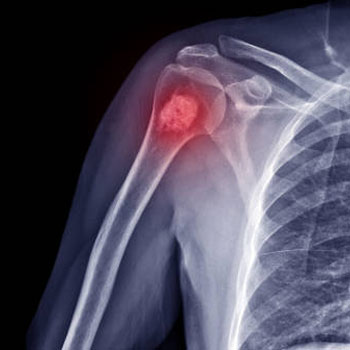

Orthopaedic oncology is a specialized branch of medicine that focuses on diagnosing and treating bone and soft tissue tumors. These tumors can be either benign (non-cancerous) or malignant (cancerous). The field also deals with metastatic tumors, where cancer spreads from another part of the body to the bones. Orthopaedic oncology aims to preserve mobility, relieve pain, and improve the overall quality of life for patients while addressing complex bone and soft tissue conditions.

People should seek medical advice if they notice persistent bone pain, swelling, fractures that occur with minimal injury, or visible lumps in soft tissues. Early consultation can make a significant difference in treatment outcomes. A trusted orthopaedic oncology hospital in Gudivada offers the right environment for early detection and proper management of these conditions.